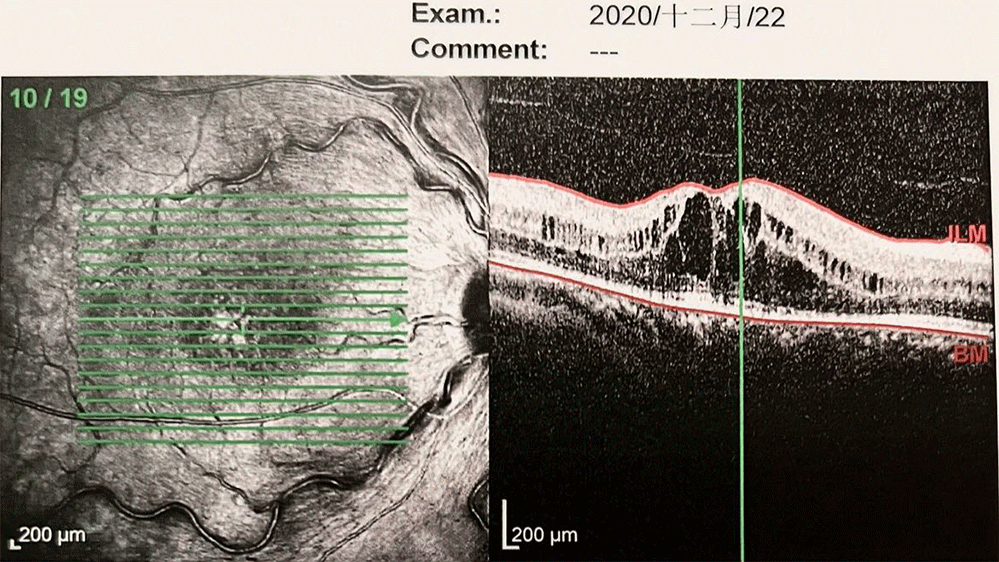

• 2020年12月22月:

患者情况】:ME复发时间并没有缩短,基本在25天左右。

治疗】:为延长治疗间隔,和患者详细建议后决定更换抗VEGF药物为:康柏西普(朗沐®)

康柏西普17次注射CRT趋势

2020.12.21-2022.8.17共注射康柏西普17针,每次注射后CRT均有不同程度下降,间隔35-55天左右,复发CRT596-687um,小数视力在0.8-0.2之间波动,末次随访视力为0.8。整体CRVO-ME呈现良好的趋势

最近一次随诊/复查

距离上次注药35天,2022.9.21

视力稳定

视力:VOS 0.8

眼压:14mmHg

继续随访